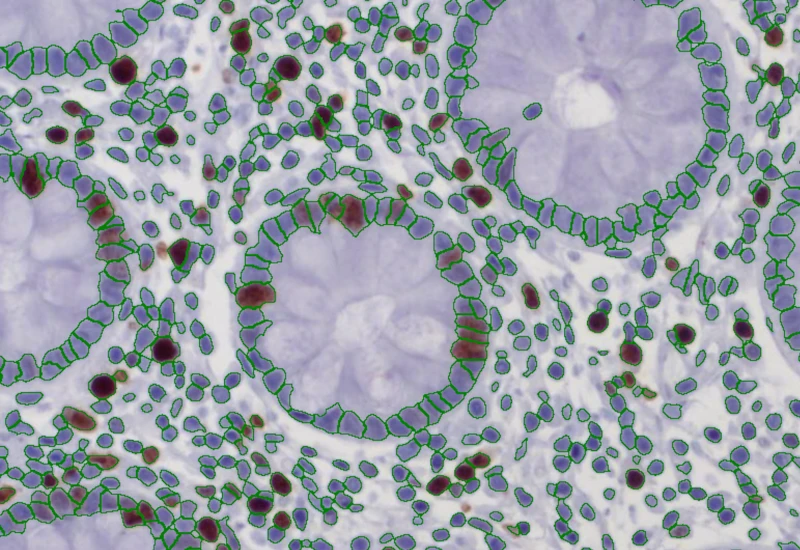

The IHC 2 App separates two markers (e.g. chromogen and counterstain) in an IHC or HC digital slide and segments single cells into nucleus, and/or perinuclear area and/or cytoplasm. Each segmented cell compartment is measured for up to 20 intensity, statistic and morphometric parameters which are displayed in scattergrams and histograms and can be exported.